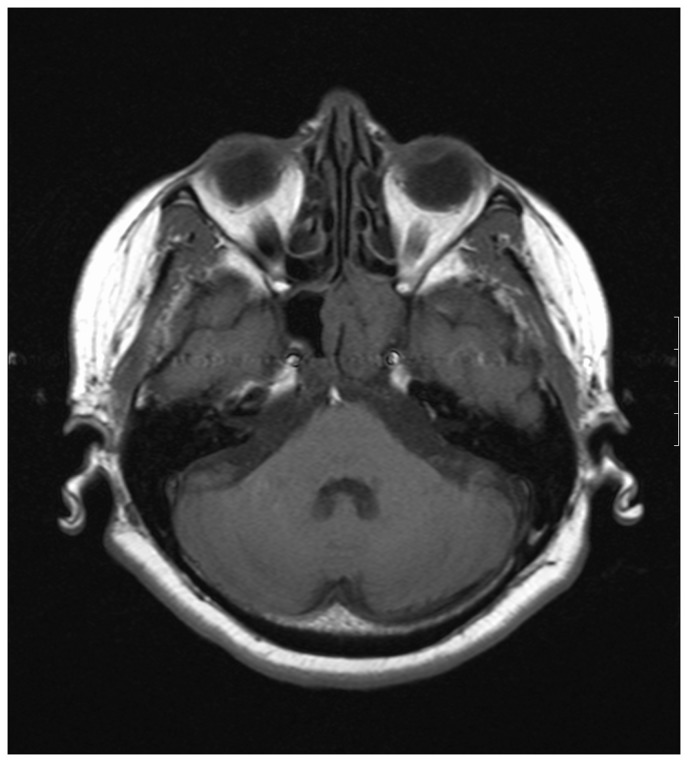

一例孤立的蝶骨真菌鼻窦炎在一个老年糖尿病患者被描述。偶然发现位于鞍区共存的肿块病变。这两个实体的重合代表了潜在的手术灾难,可能导致真菌感染的直接颅内扩散。

A case of isolated sphenoid fungal sinusitis in an elderly diabetic patient is described. A coexisting mass lesion located in the sellar region was detected incidentally. Coincidence of these two entities represents a potential surgical disaster which may result in direct intracranial spread of fungal infection.